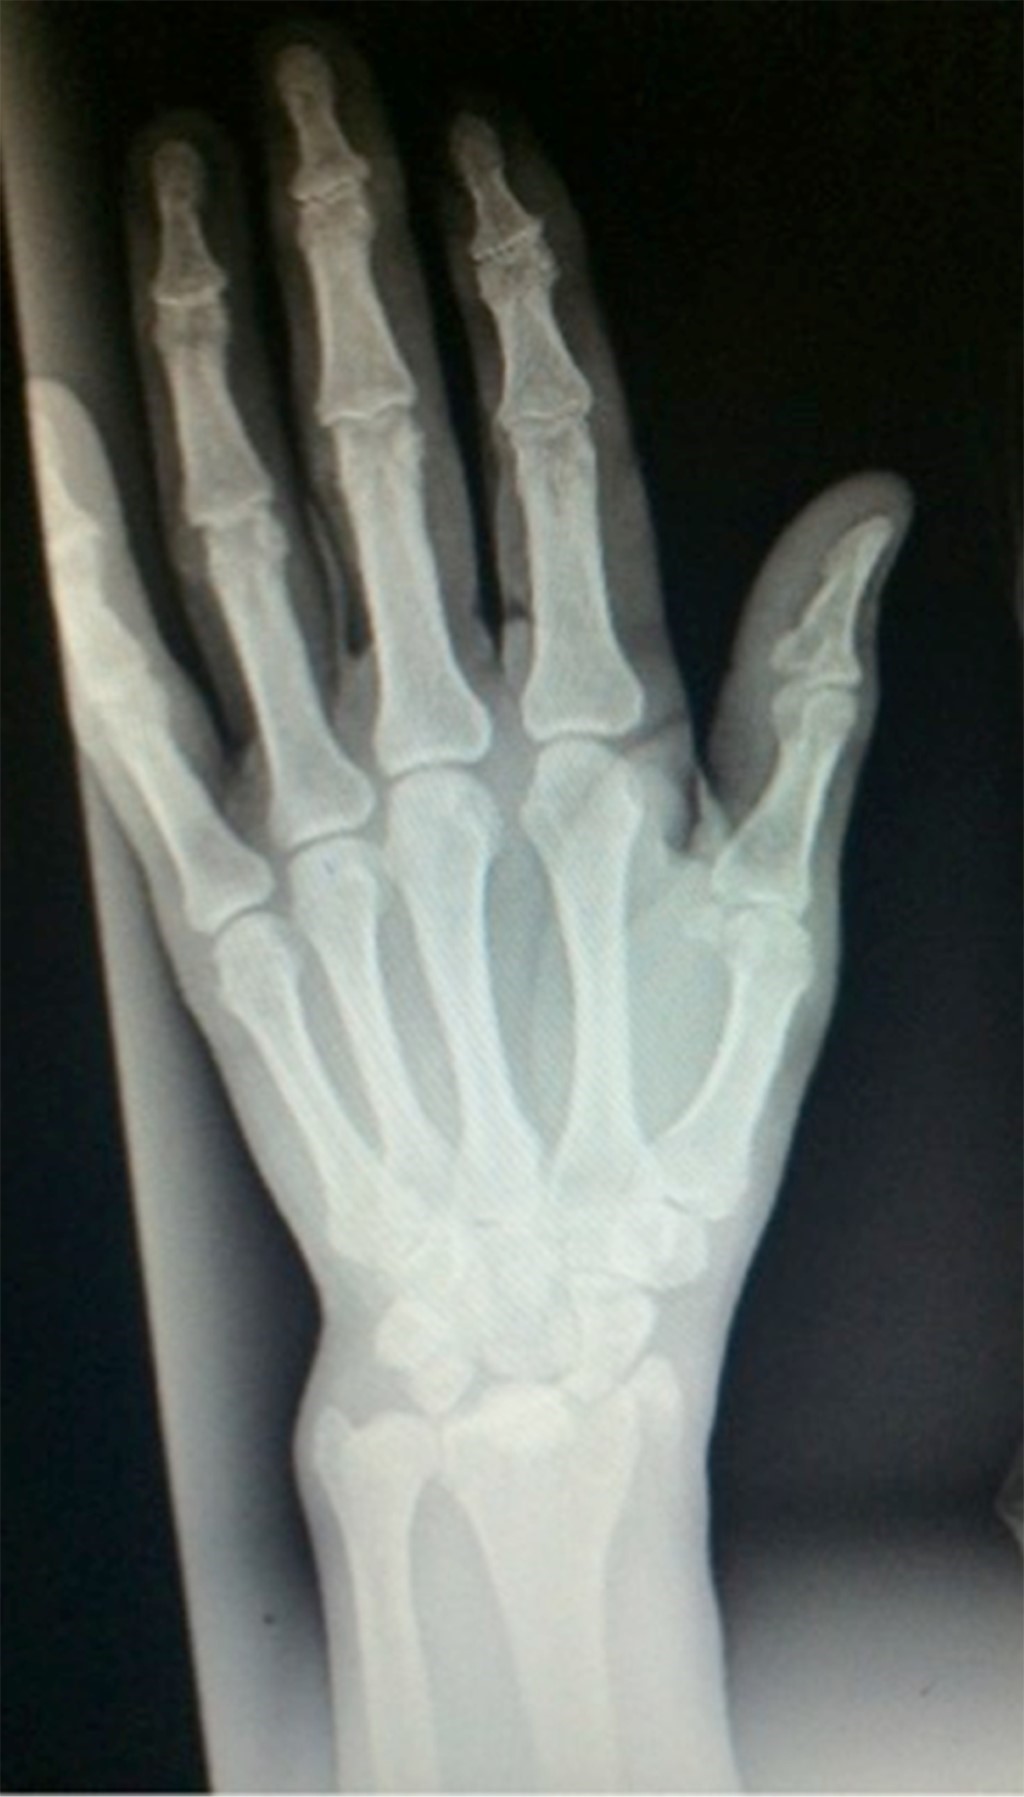

X-ray results showed a radial styloid fracture and semilunate dislocation of the left wrist (Figure 1). In addition to these findings, a lateral condyle fracture of the left femur and a radial styloid fracture of the right wrist were also appreciated.

Figure 1